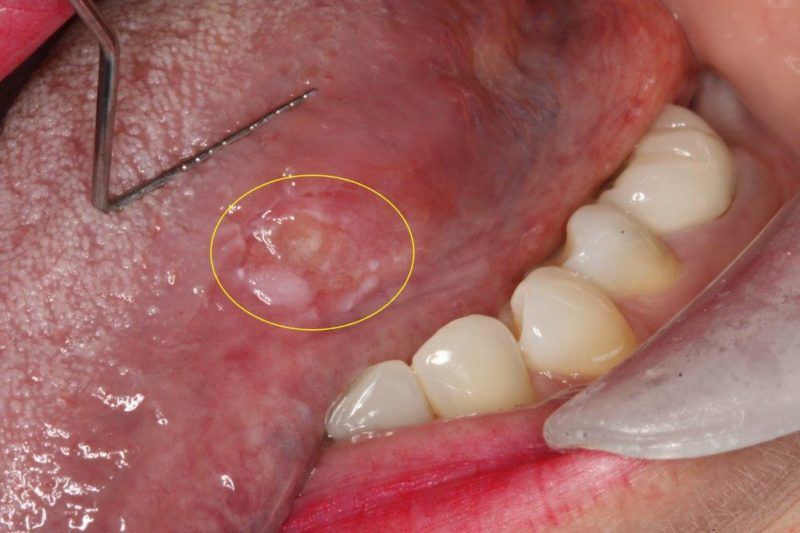

Leukoplakia

White or grayish patches inside the mouth that cannot be wiped away. Commonly found on the gums, inner cheeks, or tongue and identified during routine oral cancer screening in Lawrenceville.

Tissue Abnormalities

Unusual changes in the color or texture of oral tissue, including areas of inflammation or irregular growth patterns. Advanced oral cancer screening technology at our Lawrenceville office helps detect these early.

Oral Lesions

Persistent sores or lesions that do not heal within two weeks. Early identification through oral cancer screening at Deluxe Dentistry in Lawrenceville is critical for favorable treatment outcomes.